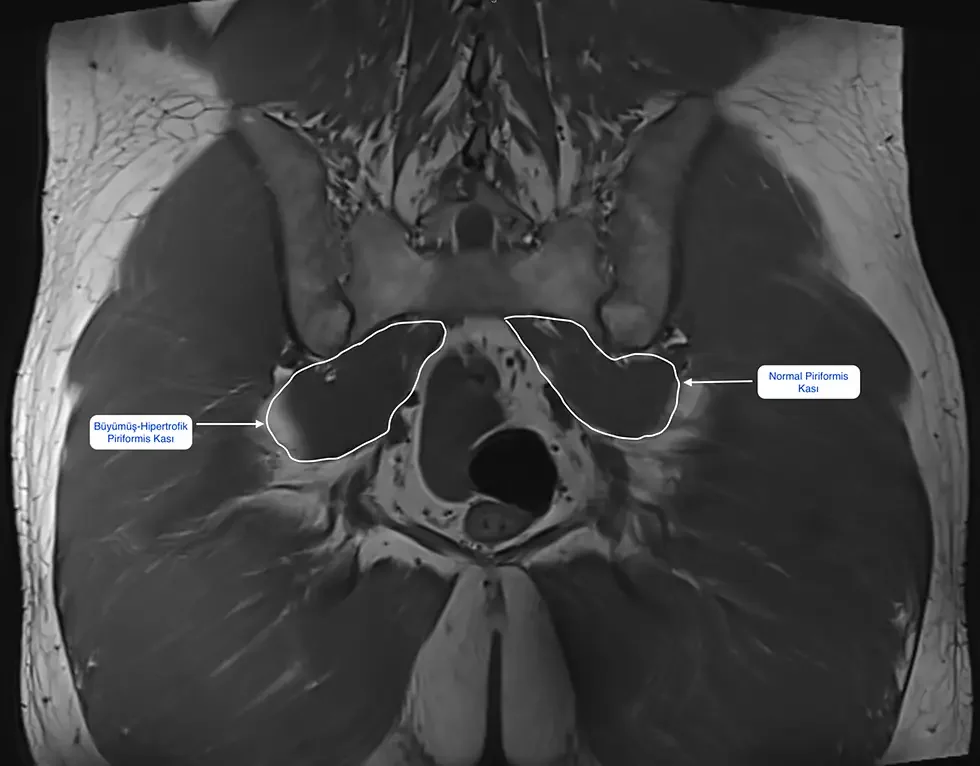

- Pelvis veya kalça MR’ı: Her hastada şart olmasa da, seçilmiş olgularda piriformis kasının şiş, kalın veya karşı tarafa göre belirgin büyük olup olmadığına bakılabiliyor.

- MR veya ultrason görüntülerinde piriformis kasında belirgin hipertrofi (büyüme) veya çevresel ödem saptanması

Teknik olarak bakarsak, MR; kasların, tendonların, sinirin ve çevre yumuşak dokuların kalitesini göstermede oldukça başarılı bir yöntemdir. Ancak piriformis sendromu çoğu zaman doğrudan MR’a bakarak “işte bu” denebilecek kadar net görüntüler vermez.

Bazı hastalarda piriformis kasının karşı tarafa göre belirgin büyük, ödemli veya sinire çok yakın olduğu görülebilir. Bu elbette tanıyı destekler. Ama MR’da her şey normal göründüğü halde klinik olarak piriformis sendromu olan pek çok hasta olduğunu da biliyoruz. Yani MR, tanıyı destekleyen ama tek başına dışlayan ya da kesinleştiren bir test değildir.